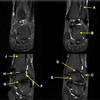

120

121

122

123

124

125

What is letter A?

What is letter B?

What is letter C?

What is letter D?

What is letter E?

What is letter F?